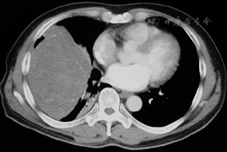

全组患者手术顺利,无围手术期死亡。全组手术时间100~300 min,平均时间191 min,术中出血100~1 500 ml,平均215 ml。2例姑息性切除病例均为Masaoka分期中Ⅳa期恶性胸腺瘤。其中1例术中探查壁层胸膜多发结节,术中切除肿瘤主体,病理证实为B3型胸腺瘤。术后予放化疗治疗。患者术后2年死亡。另1例曾于外院行胸腺瘤切除,术后复发并接受放疗治疗。患者术前有胸闷等明显压迫症状。术中见肿瘤与上腔静脉侵犯,左侧无名静脉完全闭塞。且与周围组织广泛粘连。术中切除大部分瘤体,残余部分用银夹标记术后辅助放疗。术前已获得明确病理学诊断的恶性肿瘤患者,根据具体情况行术前化疗或放疗,减少肿瘤体积进而为手术创造机会。图1所示患者为右侧巨大独立性纤维瘤,予射频消融多点治疗,减少肿瘤体积。后开胸手术,完整切除肿瘤及受侵犯的右肺下叶。